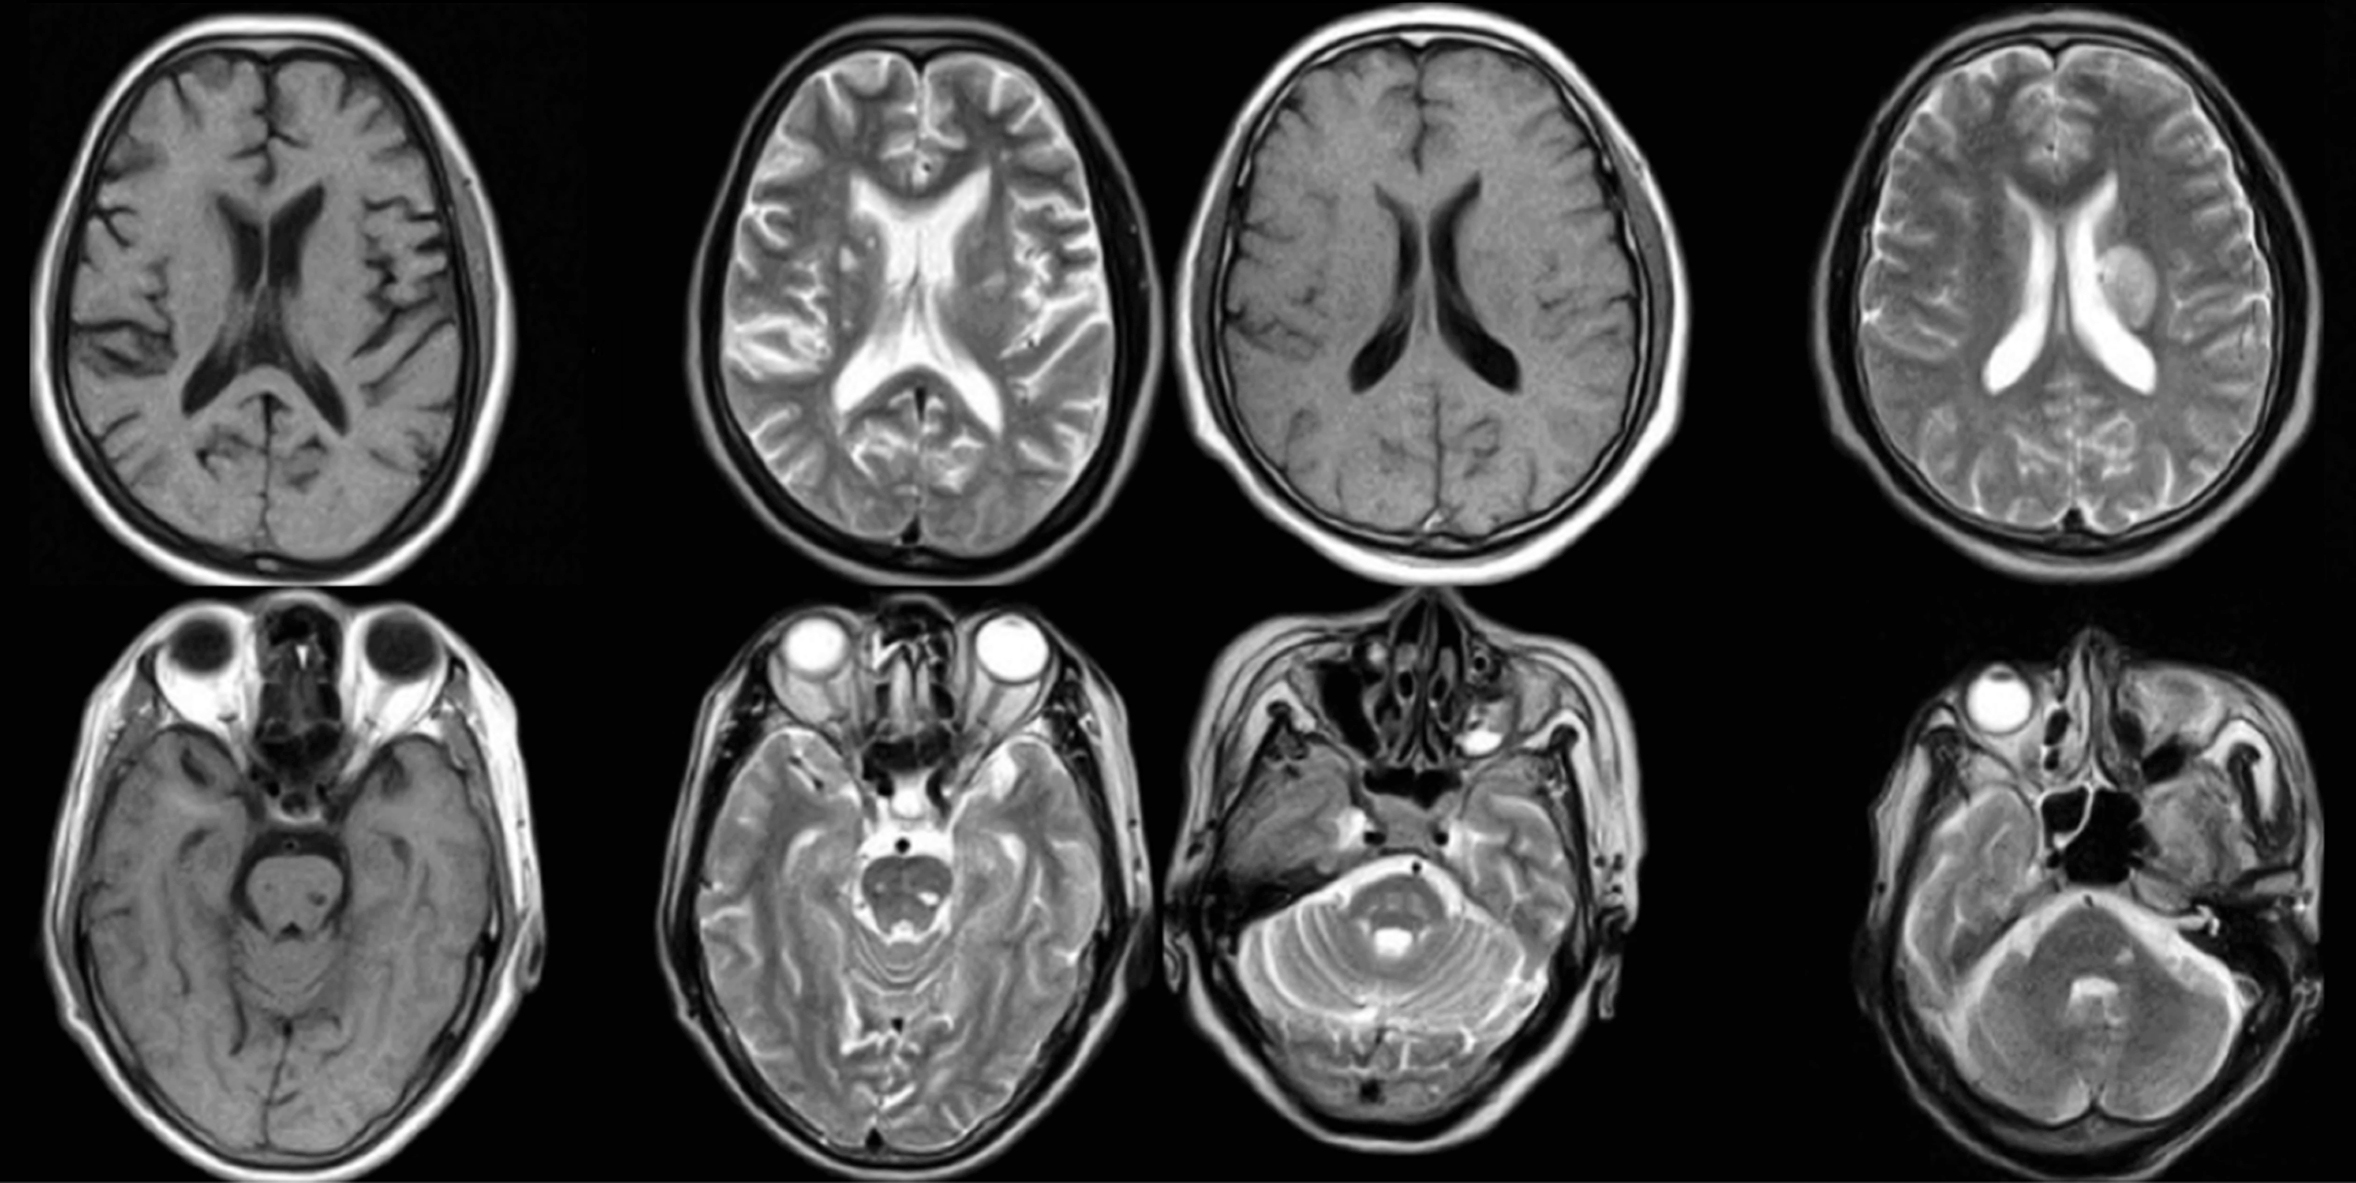

MR表现:若病变无出血,T2WI表现为脑白质、灰白质交界处和胼胝体、脑干及小脑散在、分布不对称的点片状异常高信号,T1WI呈等或低信号。若有出血灶,急性期病灶呈T2WI低信号,T1WI等或高信号,周围可见水肿信号;亚急性和慢性期出血的信号强度随时间而异。DWI对诊断超急性期及急性期脑弥漫性轴索损伤具有很高的敏感性,显示出血为低信号而水肿为高信号;SWI则对微小出血有更高的检出能力(图2-4-7)。

图2-4-7 弥漫性轴索损伤MR影像表现

单发或是多发的长T1WI,长T2WI信号

CT检查:主要可见双侧幕上半球弥漫性脑水肿及脑肿胀,灰白质分界模糊,脑室、脑池、脑裂和蛛网膜下腔变窄或消失,胼胝体、第三脑室旁、中央白质、脑干及小脑可有点、片状出血,无中线结构移位,部分病例可见蛛网膜下腔出血、脑室内血或薄层硬膜下出血。

MR检查:比CT检查更为敏感。弥漫性轴索损伤如为非出血性,典型表现为T2WI可见脑白质、脑灰白质交界处和胼胝体、脑干及小脑散在、分布不对称的点片状异常高信号,T1WI上述病灶呈低或等信号。急性期出血病灶在T2WI呈低信号,T1WI呈等信号,周围可见高信号水肿。亚急性期和慢性期出血表现为高信号。损伤后期由于脑白质损伤、轴突变性、萎缩,可使相应部位的脑室扩大。

对弥漫性轴索损伤的诊断价值而言,MRI比CT检查具有更高的敏感性,且T2WI优于T1WI。